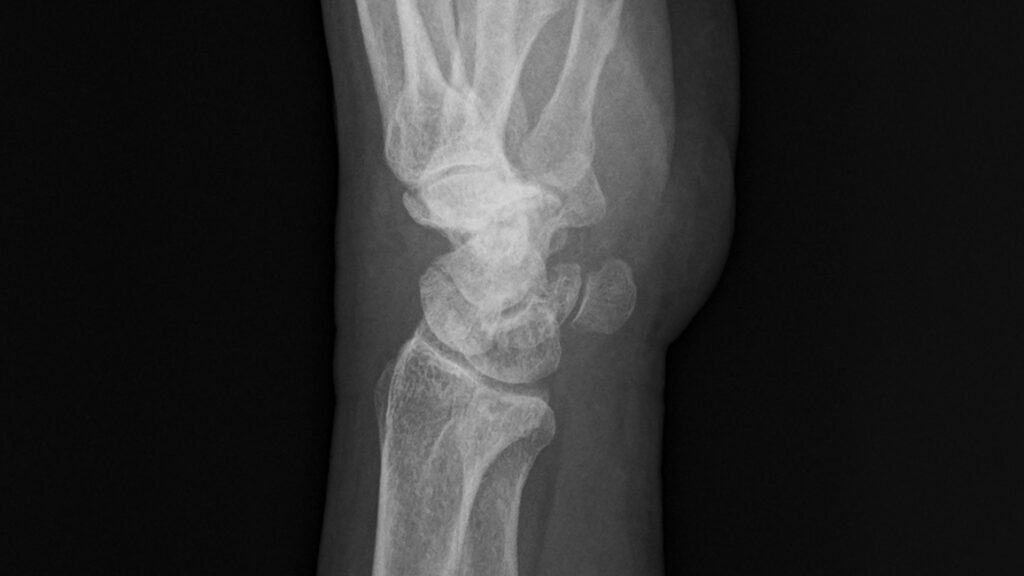

下図は手術前の左手レントゲン写真で、中央の船状骨が砕けている様子が見える。

以下の5枚は再発後、手術直前に撮影されたレントゲン写真である。正面像では舟状骨遠位部に骨折線が見え、斜位像および側面像では骨片のずれが明確に確認できる。

/レントゲン写真を角度を変えて5枚撮影